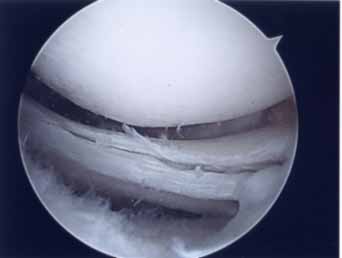

第1段階軟骨形成術

軟骨障害は最初亀裂または剥離で始まります。この状態が第一段階軟骨障害です。このことはあまり一般に知られていません。この最初の亀裂や剥離状態のうちに対処することが最も結果が良好となります。亀裂や剥離が進んでしまうと②の状態になります。

第2段階軟骨形成術

軟骨の剥離や亀裂が①より少し進んだ段階です。放っておくとさらに軟骨欠損が進み軟骨障害は広くなり且つ深くなります。この段階ではまだドリリングなどの操作は不要です。第3段階軟骨障害との間は幅広く関節鏡で見てみないと最終的に判断できません。この段階では手術結果は比較的よく平均75~90点ほどになります。